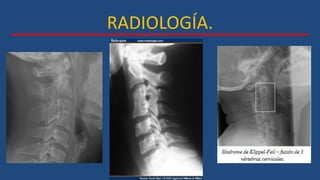

RADIOLOGÍA.

 AP, lateral y oblicua de columna cervical.

• Fusión de 2 o más cuerpos vertebrales.

 Proyecciones laterales en flexión-extensión.

• Identificación de segmentos con exceso de

movilidad.